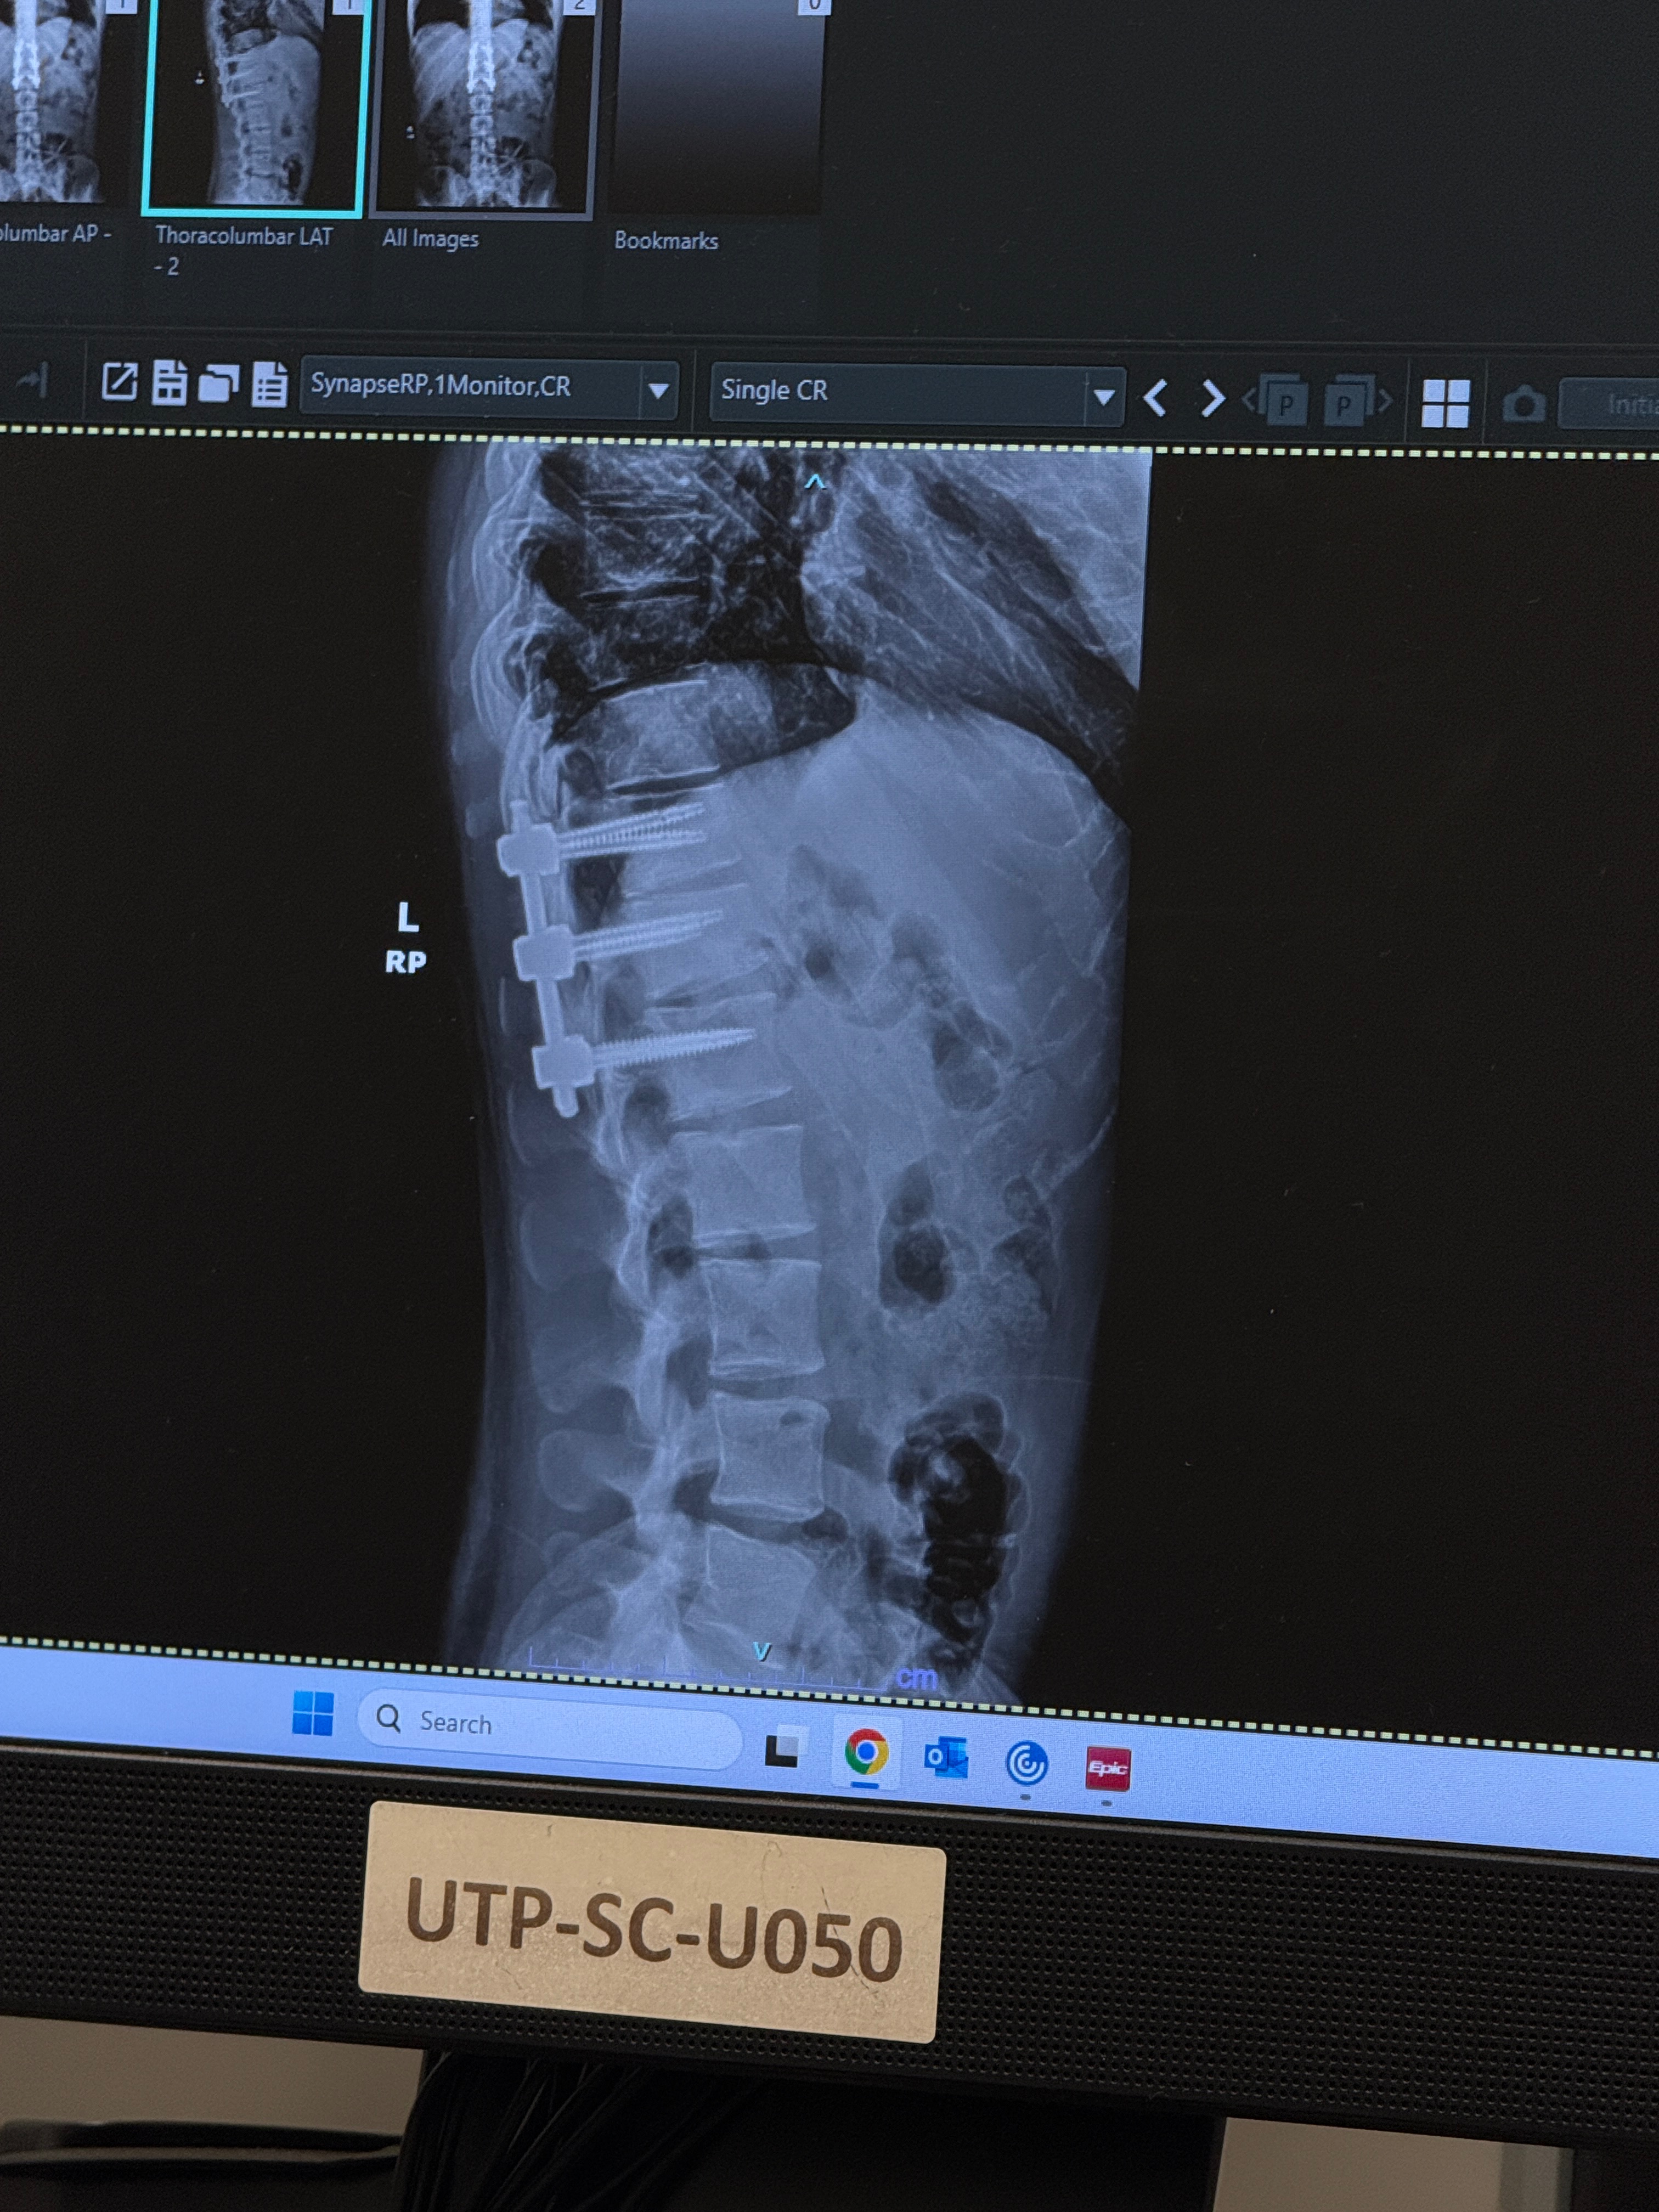

Yesterday (1/25) at about 12 noon, Johnathan Spence was outside and was struck by a falling limb during the ice storm. We called 911, but only the fire department was able to get to us due to the roads being extremely iced over. The fire engine was able to fit him inside on a backboard and met the ambulance halfway. When he finally arrived at the hospital, they found out his back was broken and he was in critical condition. He needed neurosurgery immediately. The neurosurgeon was not able to get there due to ice, and there was no way to fly him out yet. We waited all night, and finally, at 9 this morning (1/26), the neurosurgeon arrived, and he was able to have the surgery!! He is now in ICU and is trying to recover. They are going to get physical therapy helping him try to have feeling in his legs as soon as possible. There still is not a certainty that he will ever walk again, but we are trying to be optimistic. We are asking for lots of thoughts and prayers! Thank you all!